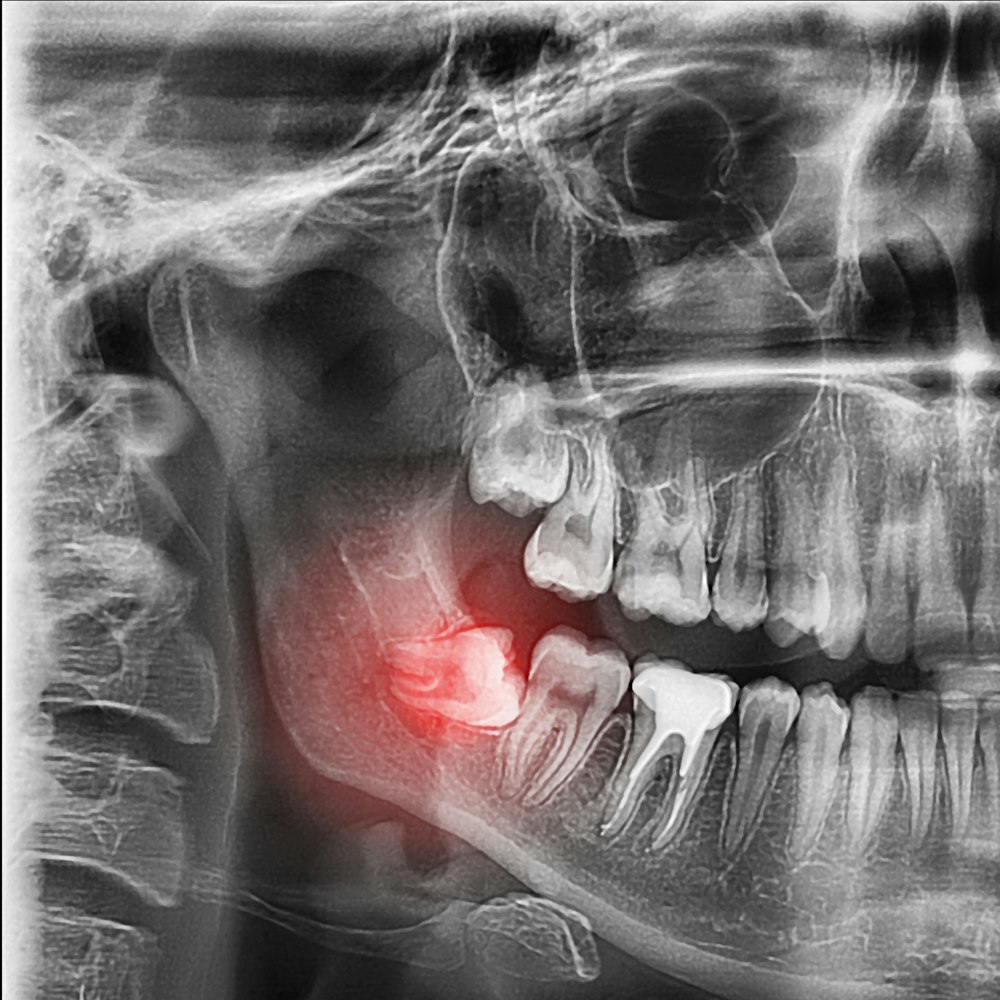

When your wisdom teeth grow in, they can become impacted and cause overcrowding, pain, and oral health complications.

Our dentists will make a small incision in your gums to access the tooth. Impacted teeth may require a small portion of bone to be removed for access.